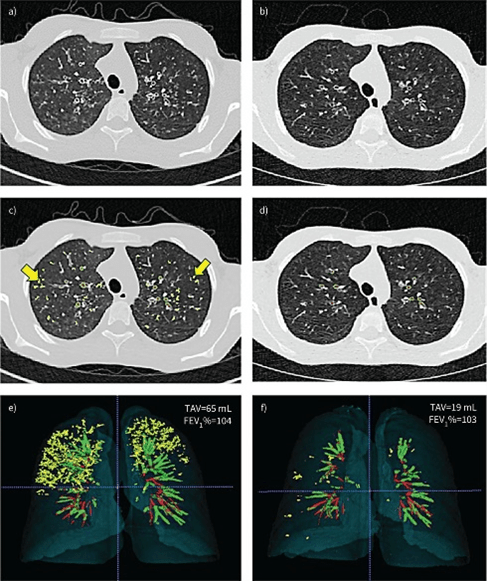

Artificial Intelligence (AI)

We have demonstrated that an AI-driven semantic quantification of lung structural alterations is feasible in CF by building an automated scoring system. Clinical validation expects that a biomarker reflects the clinical severity, correlates to a known outcome and may improve with an effective therapy. Our objective was to develop an algorithm enabling recognition of five structural alteration hallmarks on CT slices. We then aimed to assess the clinical validity of the quantitative scoring method by correlating to the patient's disease severity, as assessed by the CT Brody score. Additional objectives were to support the clinical validity to correlate to PFTs, assess variations in patients with and without lumacaftor/ivacaftor, and evaluate the reproducibility.

Our studies have demonstrated that AI-driven quantitative measurement of lung structural abnormalities on CT scanning in CF is, indeed, feasible, and can provide clinically important information in a broad range of patients using a wide range of CT scanners and CT techniques. The system showed good similarity and very good agreement with ground-truth identification of expert observers’ abnormalities, but dramatically quicker, with high reproducibility. Volumetric measurements showed a strong correlation to PFTs and a well-validated visual CT score at several time-points. The automated quantifications were found to sensitively detect longitudinal changes, either a reduction in CF patients with lumacaftor/ivacaftor treatment or an increase during the natural course of the disease. As a fully automated outcome measurement, the reproducibility was almost perfect.